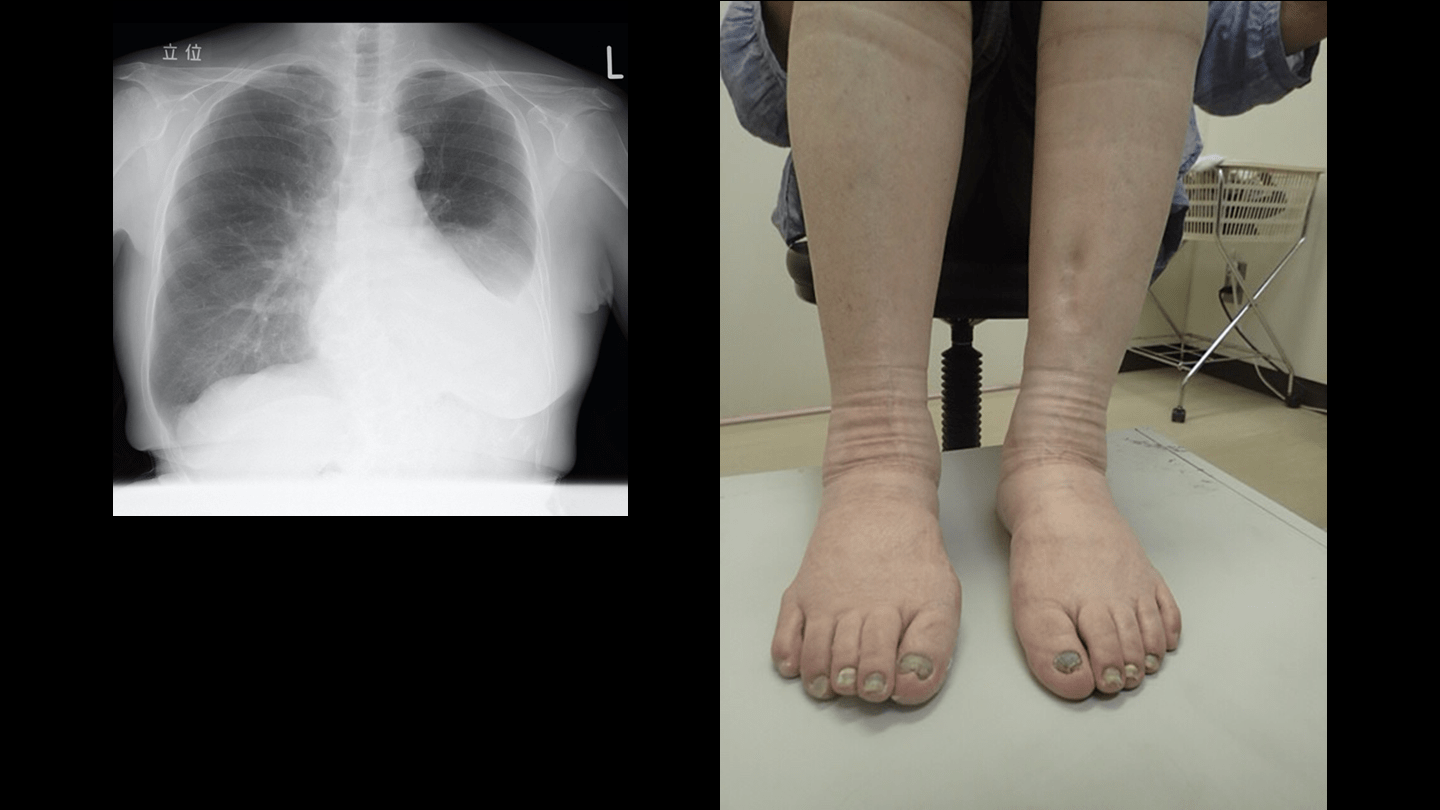

ブシラミンによる Yellow nail syndrome. (まれな疾患だが、報告は多数ある) ブシラミン中止により爪の所見が改善した推移を画像で示した報告はない。(わずかな新奇性) J Gen Fam Med. 2017; 18: 479-480